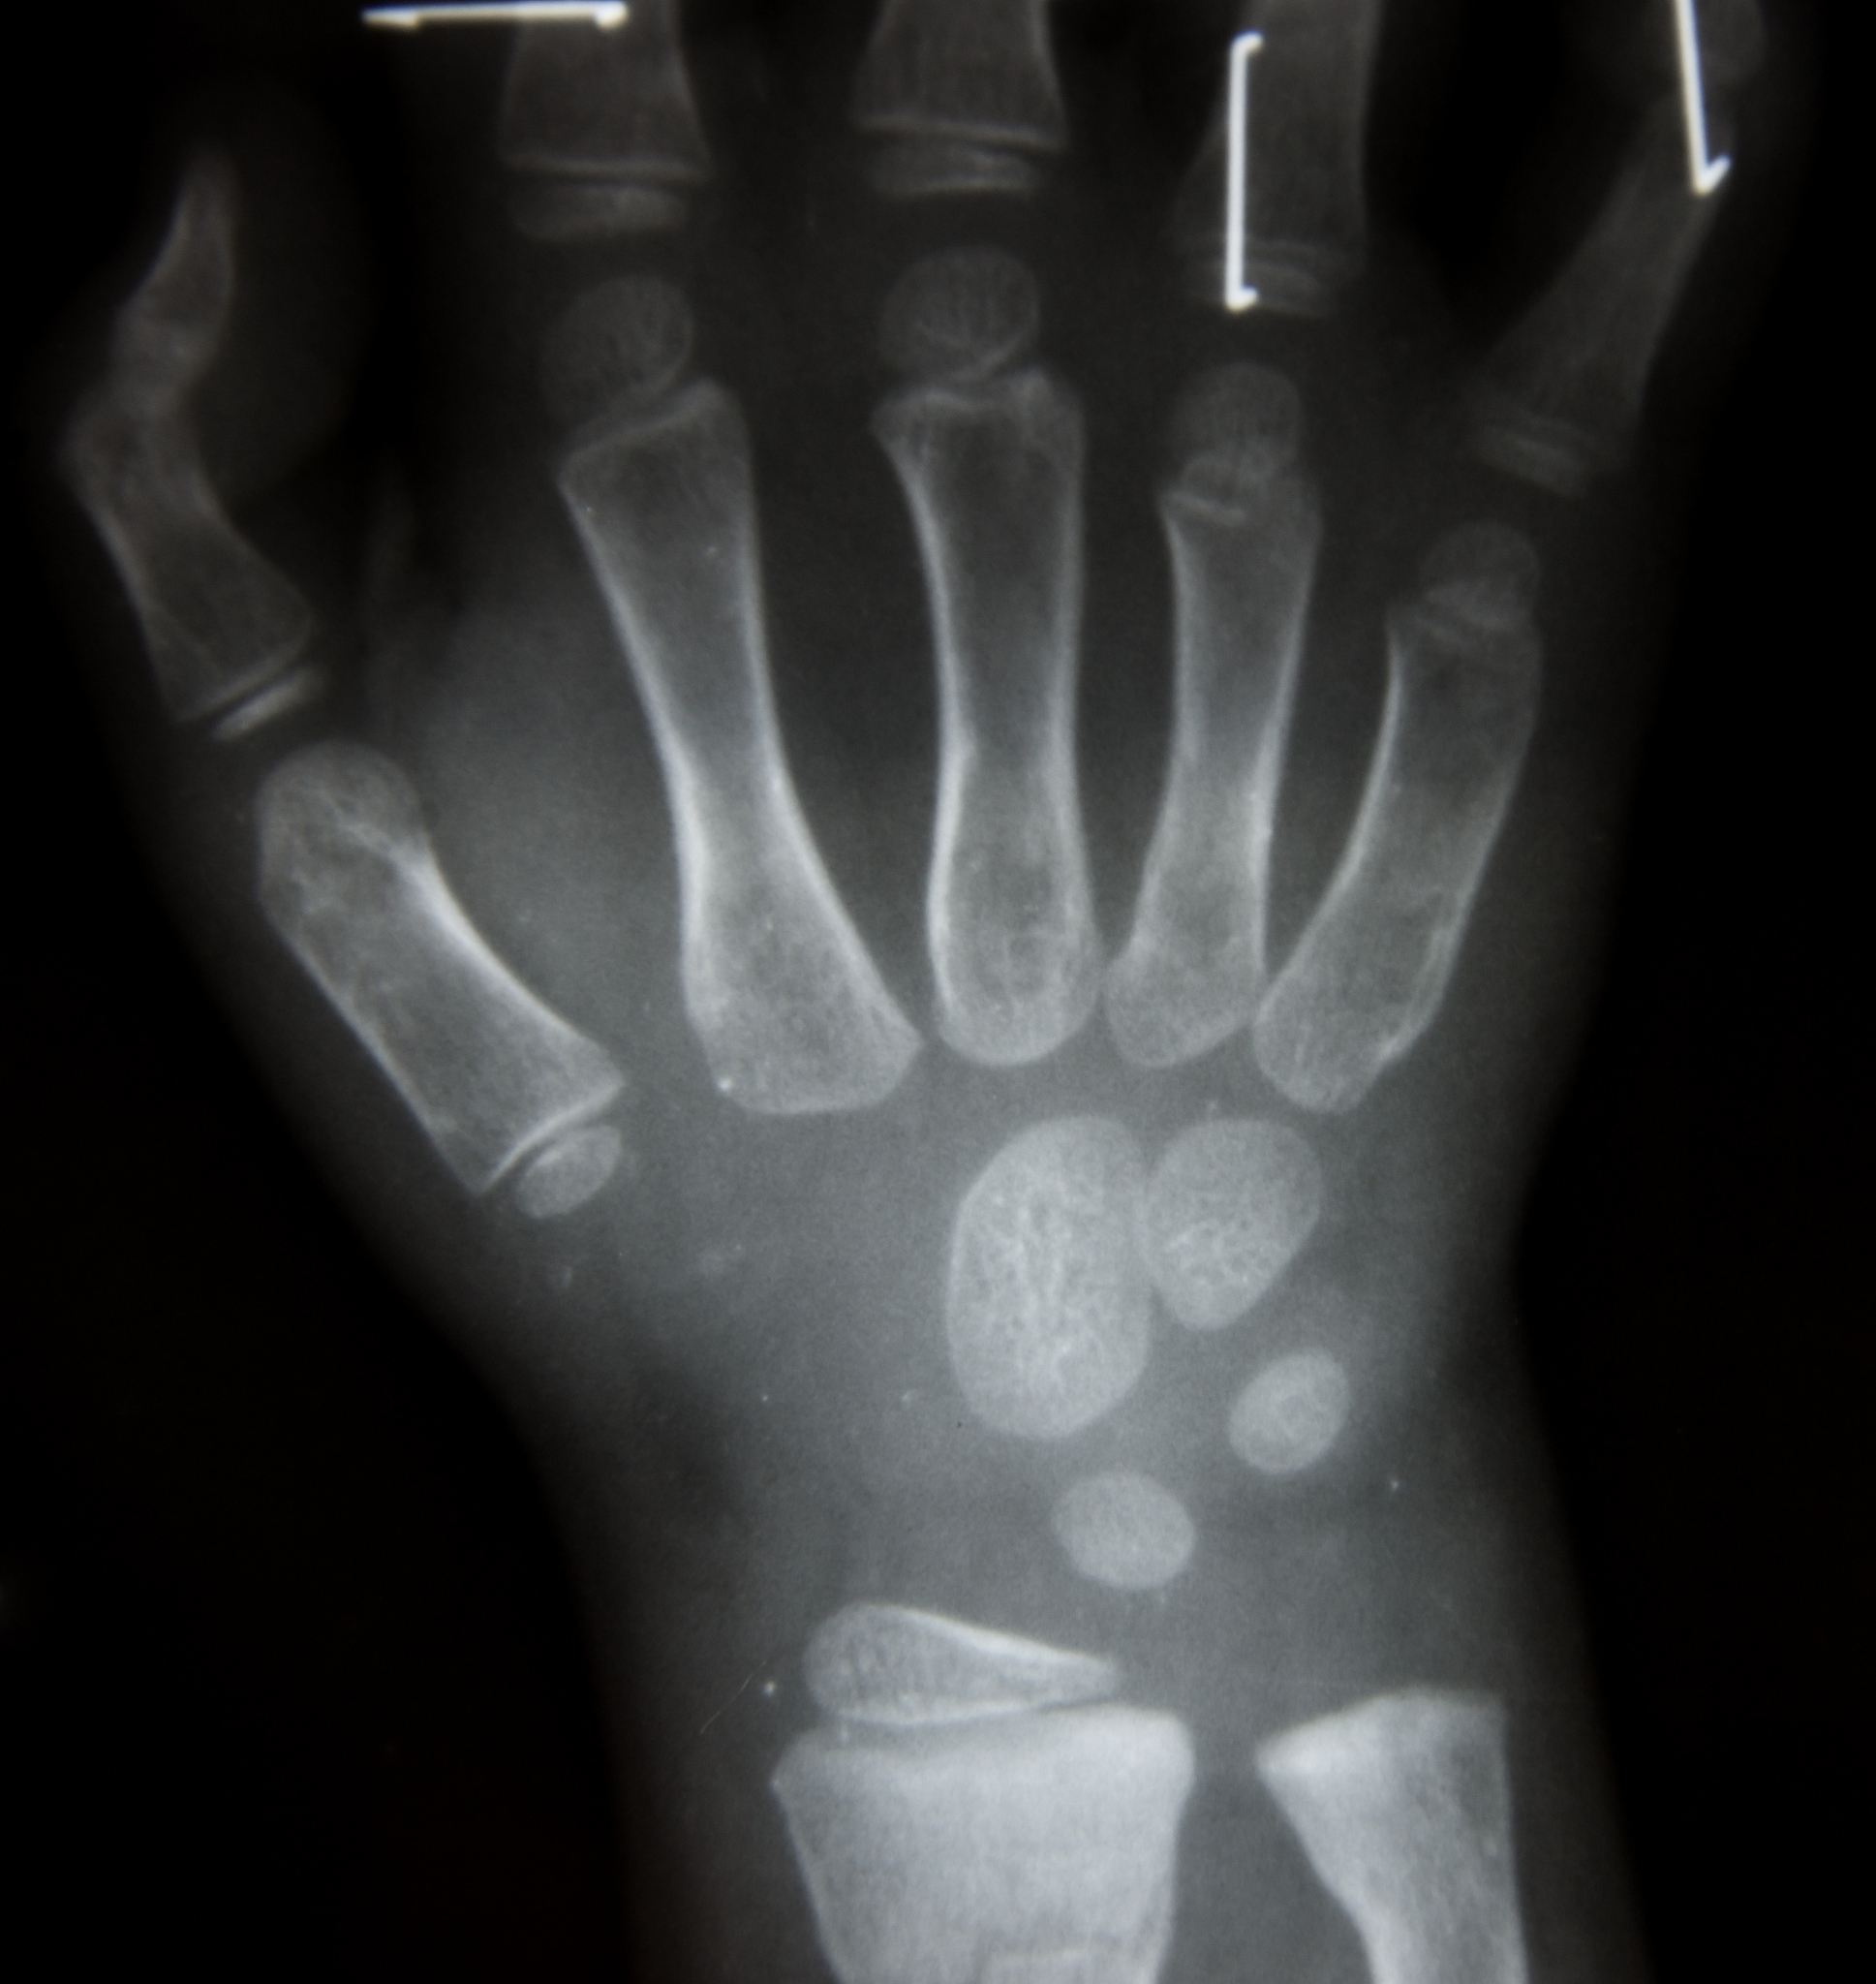

X线拍片法是通过对儿童的手腕、手掌、膝盖等部位进行X线拍片,然后根据骨骼发育情况来判断其骨龄。这种方法主要依赖医生的经验和专业知识,需要通过对多个部位的不同角度的拍片进行分析。

传统的骨龄预测方法虽然准确度较高,但需要专业人员进行操作,且存在较大的主观性和人为误差。同时,这种方法需要对儿童进行辐射检查,可能对儿童的健康造成一定的影响。因此,现在已经逐渐被计算机辅助骨龄预测方法所取代。